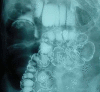

Ileocolic Intussusception - A rare cause of acute intestinal obstruction in adults; Case report and literature review

Colonic Intussusception although common in children, is a rare cause of acute intestinal obstruction in adults. The etiology, clinical presentation and management of this condition is different in adults as compared to children. Pre-operative diagnosis is usually difficult due to the non specific and intermittent nature of the symptoms. CT scan can be a helpful adjunct in establishing the diagnosis. We present a case report of adult ileocolic intussusception with classical radiological signs and operative findings. A brief literature review is also presented with emphasis on the controversy of reduction of the intussusception before resection.